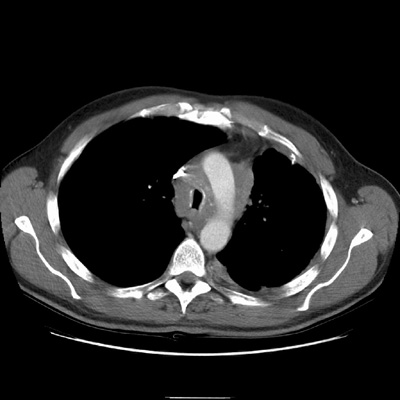

Extensive tuberculosis:

The patient below presented for evaluation of an abnormal CXR. The CT revealed bilateral extensive cavitary consolidations (essentially replacing the left lung), a large cavitary lesion in the right apex, and multiple scattered nodules and "tree-in-bud" opacities. The patient was found to have active TB.